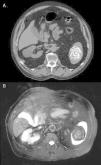

A 75-year-old male farmer presented for an abdominal CT scan because of a nonspecific, longstanding abdominal discomfort, fatigue and appetite loss. Although there were no other remarkable imaging findings, an unusual pattern of multiple, thinly, concentrically lamellated calcifications resembling targets was found in the spleen (Fig. 1A), also characterized on a further MRI work-up (Fig. 1B). Such isolated radiological finding raised suspicion of brucellosis. Laboratory tests for tuberculosis, histoplasmosis, HIV, and echinococcosis were all negative. A diagnosis of isolated splenic brucelloma was made on the basis of a positive Brucella IgG ELISA test, clinical history, and imaging findings.

Peripheral or central gross calcifications with a snowflake appearance are a common finding in hepatosplenic brucellomas (83–100% of cases),1 although absolutely nonspecific. Early radiograph descriptions, however, have reported on a characteristic concentrically lamellated pattern of splenic calcifications in chronic brucellosis,3 which unfortunately has not been demonstrated after the advent of CT,1 probably due to the rarity of splenic brucellomas and the much larger trend for an uncharacteristic gross appearance. Thus, to the best of our knowledge, this is the first report to demonstrate CT and MRI findings of this pathognomonic pattern of calcifications in splenic brucellomas since its earlier radiographic descriptions. Although exceedingly rare, awareness of this typical pattern may be useful for raising clinical suspicion, especially because diagnosis of chronic brucellosis may be sometimes misleading due to nonspecific clinical presentation.